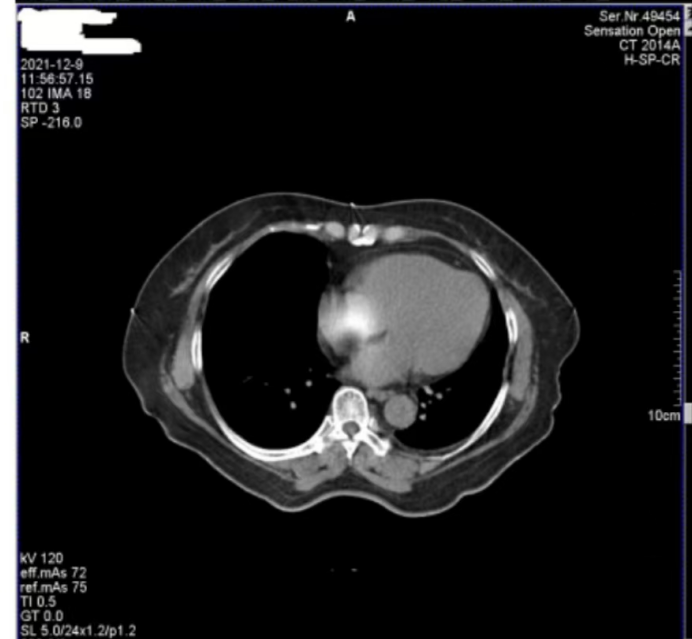

醫(yī)院反映,西門子Definition型CT機在進行患者掃描時,圖像上會偶發(fā)兩種偽影。一種是斜線狀偽影(圖 1),另一種是中心不規(guī)則高密度偽影(圖 2)。其中,斜線狀偽影對診斷影響較大,時常導致醫(yī)生無法準確判斷患者病灶情況,醫(yī)院希望我們盡快排查并解決問題。

圖2

接著,我們將目光轉向圖 2 中的中心不規(guī)則高密度偽影。為了找出偽影成因,我們對設備的多個關鍵部件進行了檢查。首先查看了玻璃條、探測器表面以及準直器表面,確認這些部位是否沾有造影劑,因為造影劑殘留有時會導致偽影產(chǎn)生,但檢查結果顯示這些部位均干凈無污。

隨后,我們檢查了特氟龍濾線器部件。特氟龍部件采用金屬材質,具有較高的穩(wěn)定性,通常不會出現(xiàn)斷裂等情況,因此可以排除因特氟龍部件異常導致偽影的可能??紤]到這種中心偽影是偶發(fā)出現(xiàn)的,我們開始推測其他可能性。結合球管的結構和工作原理,我們懷疑是球管內部存在雜物。球管內部有油路循環(huán)系統(tǒng),若有雜物混入其中,在曝光過程中,當雜物恰好處于出射線的位置時,就會對射線產(chǎn)生干擾,從而在圖像中心形成不規(guī)則的高密度偽影。